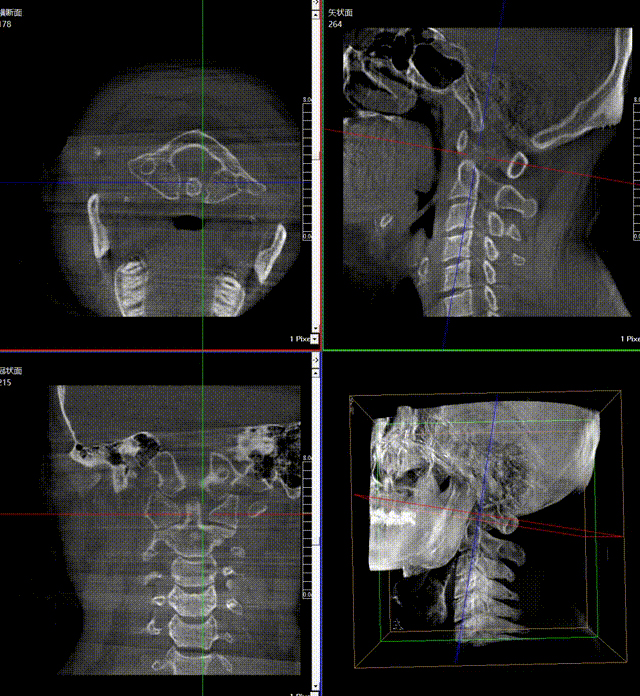

通常上颈椎的手术是非常复杂的,因为医生要把钉子打在上颈椎这样一个很狭小的通道里面,周围都是重要的神经血管,一旦损伤到颈椎,就有可能造成病人的死亡。随着医学影像技术的不断发展,在三维影像的引导下,整个打进去的通路能够完全的展现在我们的眼睛里,让这种复杂的手术变得简单了,更多的医生就可以去开展这样的手术了,也会有越来越多的病人从中获益。